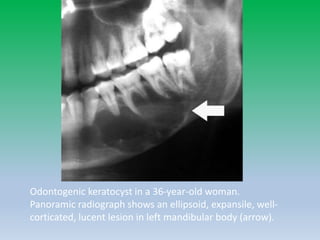

Odontogenic keratocyst

(keratocystic odontogenic tumor)

• Keratocystic odontogenic tumor was formally known

as “odontogenic keratocyst” but recently was

categorized as an odontogenic tumor rather than a

cyst.

• Benign but locally aggressive developmental

odontogenic tumor that is most commonly located

in the mandibular ramus and body.

• Adults in the 2nd-4th decades of life and represent 5–

17% of all jaw cysts.

Odontogenic keratocyst in a 36-year-old woman.

Panoramic radiograph shows an ellipsoid, expansile, well-

corticated, lucent lesion in left mandibular body (arrow).